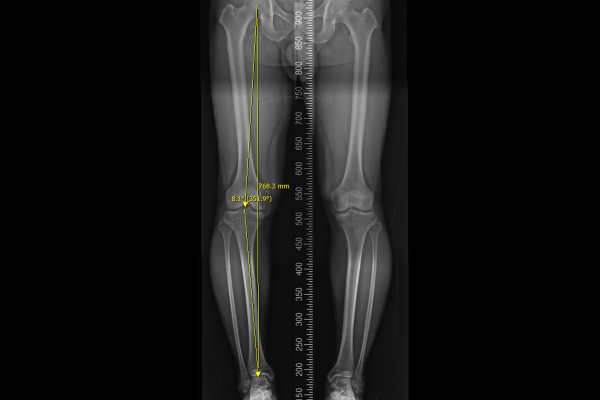

다리 전체 정렬을 확인하는 검사인 Scanogram 촬영 사진을 보시면, 오른쪽 다리 각도가 정상범위인 5도 이내를 벗어난 8.1도로 오다리 변형이 확인되었습니다.

수술은 성공적으로 마치게 되었고, 수술 후 X-RAY를 보면, 기존에 안쪽에 있던 체중선이 중간에서 살짝 바깥쪽으로 잘 이전되었고, 다리축이 일자로 교정되었음이 확인됩니다.